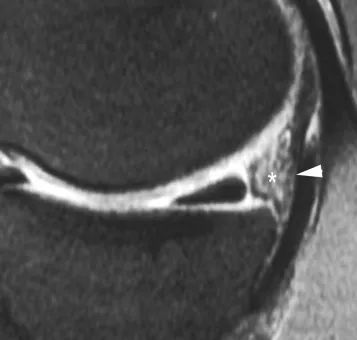

Elles se traduisent par un décalage de 5 mm du ménisque supérieur par rapport au bord postérieur du plateau tibial sur les clichés sagittaux (Fig. 11), ou une insertion liquidienne entre la base du ménisque et le plan de la capsule articulaire.

Figure 11 Décollement de la corne postérieure du ménisque.Vue sagittale de la densité de protons.Le ménisque séparé est déplacé vers l'avant.Il existe une large zone d'hypersignal (*) entre la base du ménisque et la capsule postérieure (flèche).